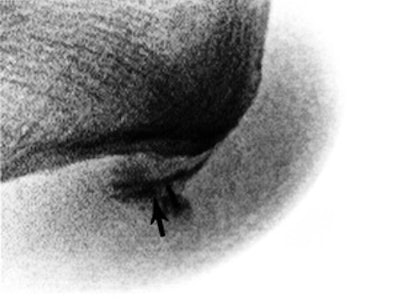

In 54 patients identified with pain at the origin of the plantar fascia, 47 had relief >50% of their pain by a single perifascial injection (figure 2).

FIGURE 2. (A) This sagittal fat-suppressed MR image shows thickening of the plantar fascia origin (hollow arrow) and edema within the fat pad (black arrow), near a skin marker.

(B) The patient undergoing a fluoroscopy-guided injection with the contrast (black arrow) tracking along the fascia origin. The patient reported complete pain relief from the anesthetic.

There were no complications from injection, though three patients reported temporary worsening of the plantar heel pain. Surgery was recommended to eight patients with recurrent pain and successful pain relief from an injection. Five patients underwent excision of the origin of the plantar fascia and have been followed a minimum of 1 year. There were no complications from the surgery and all patients reported functional improvement, though none had pain relief equal to the maximum improvement from an injection. All five surgical pathology specimens demonstrated abnormality of the fascial tissue.